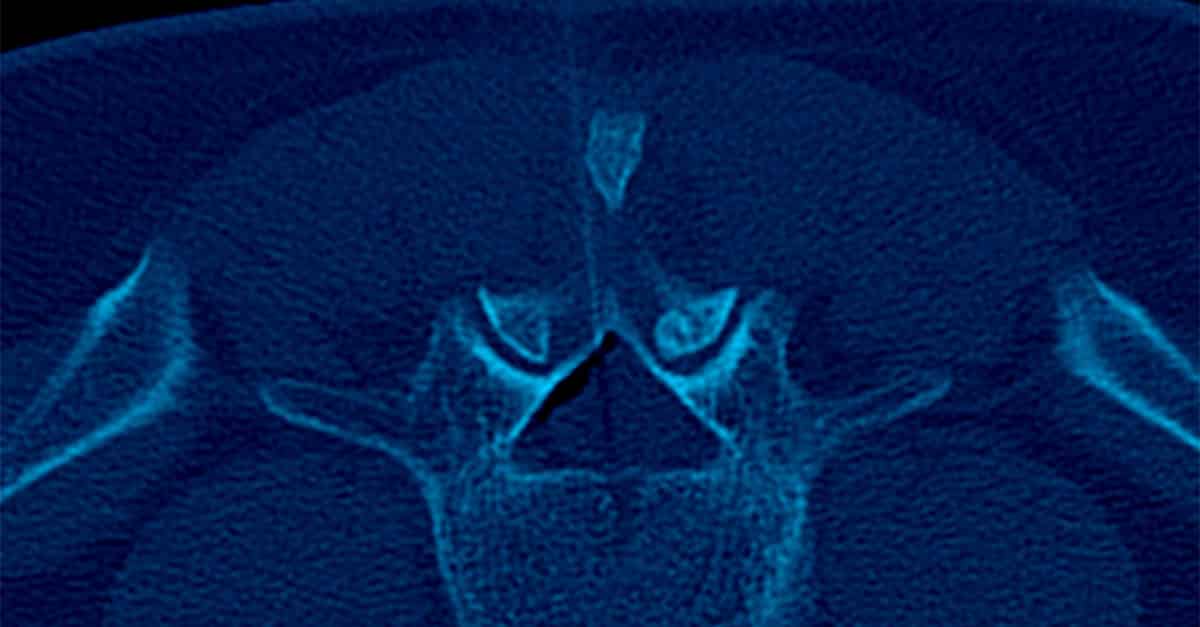

Shoulder pain can take over your life, making it feel like you’ve lost control of your movements and aren’t interested in anything. If you’re dealing with severe shoulder pain that’s lasted weeks or months, your healthcare provider might suggest cortisone therapy for the painful area as part of your recovery plan. This article will take a closer look at the role of interventional radiology in treating shoulder pain. For more details: https://shorturl.at/rE7zs